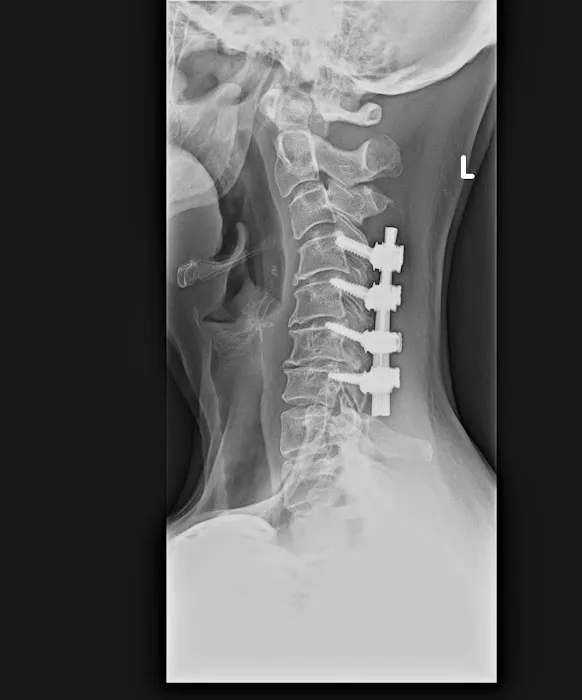

Chiropractic care is a healthcare profession focused on the diagnosis, treatment, and prevention of musculoskeletal disorders, with a primary emphasis on the spine and its impact on the nervous system. While traditional chiropractic often involves manual adjustments that may produce joint cavitation sounds (cracks), specialized approaches like Atlas Orthogonal chiropractic offer a distinctly different experience. This technique focuses on the Atlas vertebra (C1), the uppermost bone in the spine, and its relationship with the skull and the rest of the spinal column. Even a slight misalignment in this crucial area can impact the entire nervous system, leading to widespread issues. Dr. Thomas at Atlas Orthogonal Chiropractic, LLC, utilizes this highly precise, gentle method to realign the Atlas, often without any cracking. This precise adjustment aims to restore proper communication between the brain and body, alleviate pressure on nerves, and allow the body to heal naturally. This approach, combined with other therapeutic modalities, offers a powerful, non-invasive path to relief and long-term wellness.

Atlas Orthogonal Adjustments: This is the cornerstone and specialty of the practice. Utilizing a precise, gentle instrument, Dr. Thomas makes subtle adjustments to the Atlas vertebra (C1), without any twisting, popping, or cracking. This method aims to restore proper alignment of the head and neck, alleviating nerve pressure and allowing the body's natural healing processes to take over.

Car Accident Injury Rehabilitation: Dr. Thomas has proven experience in effectively treating injuries sustained from car accidents, such as whiplash and persistent neck pain, providing crucial relief and recovery support.